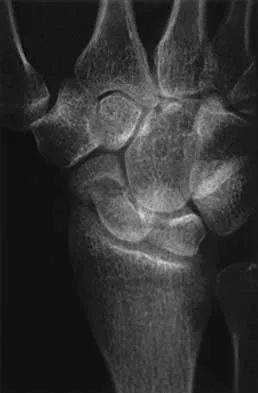

The condition shown in Figures 9a and 9b is most likely the result of

Explanation

The clinical photograph and radiograph show gout, which is the result of urate deposition in the joint and soft tissues. Radiographs frequently reveal periarticular erosions. The crystals are intracellular and negatively birefringent under the polarized microscope. Treatment for acute flares include colchicines, indomethacin, and corticosteroids (including injections). Medications such as allopurinol help prevent recurrent flares. Tophi such as that seen in this patient are often confused with and associated with infection. Wortmann RL, Kelley WM: Crystal-induced inflammation: Gout and hyperuricemia, in Harris ED, Budd RC, Firestein GS, et al (eds): Kelley's Textbook of Rheumatology, ed 7. New York, NY, Elsevier Science, 2005, pp 1402-1429. Trumble TE (ed): Hand Surgery Update 3: Hand, Elbow, & Shoulder. Rosemont, IL, American Society for Surgery of the Hand, 2003, pp 433-457.

References: